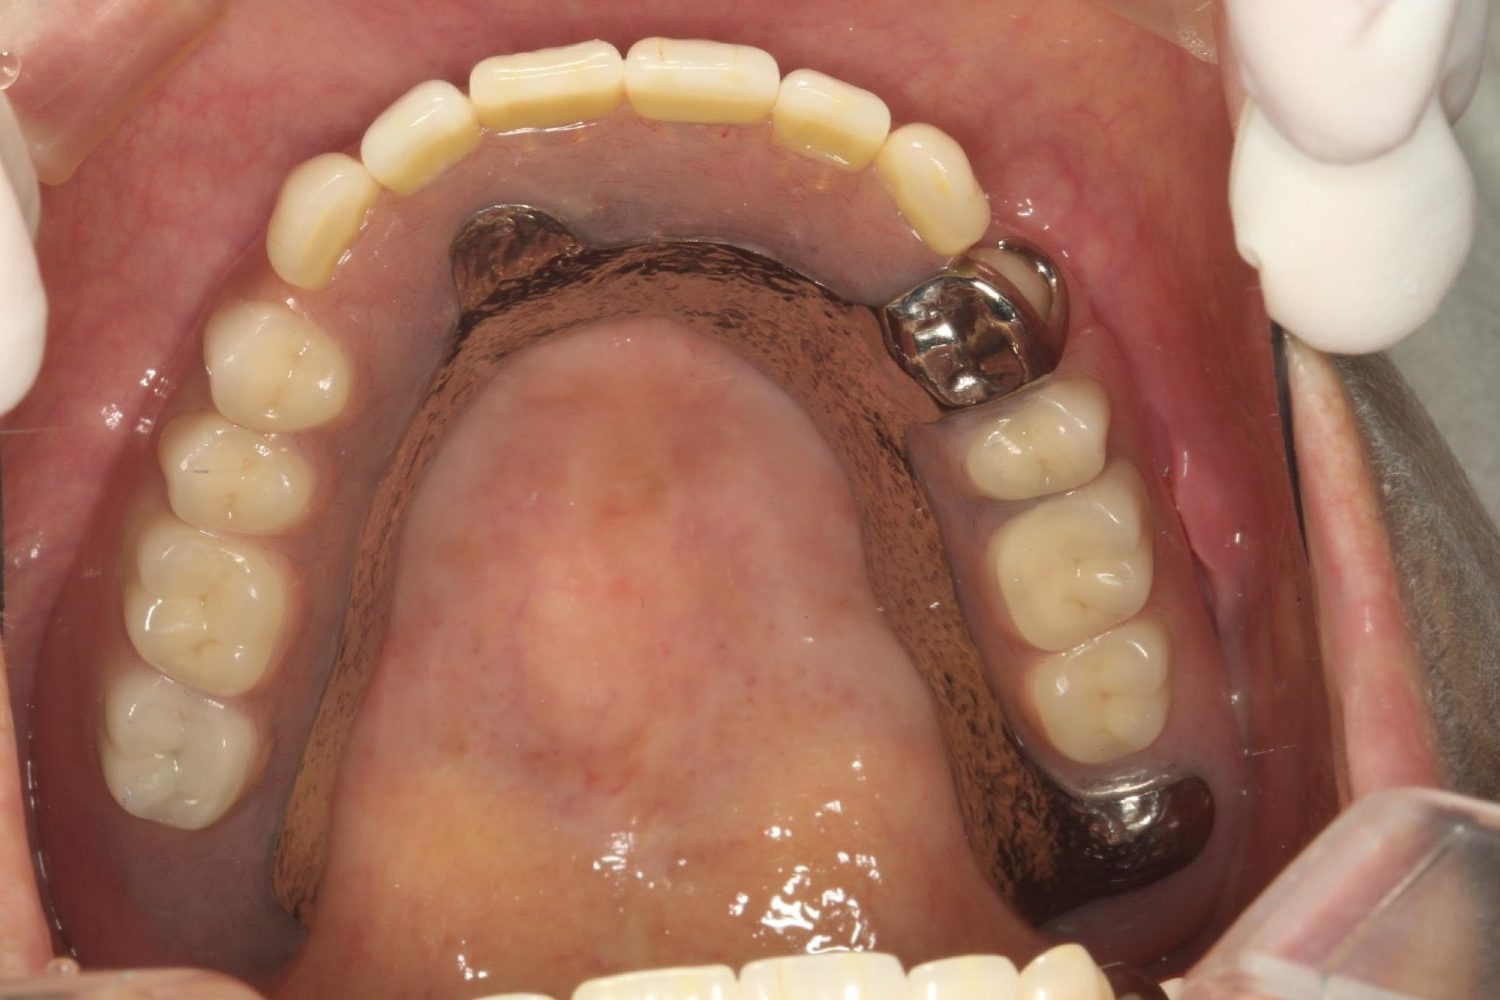

インプラント治療の症例紹介④

Before

After

主訴

義歯による疼痛

治療内容

下顎舌側に骨隆起があり義歯困難な状態。保存不可能な歯の抜歯を行い、インプラントを埋入し咬合再構成を行った。

治療費

2,851,200円(税込)

治療期間

29ヶ月

通院回数

26回

想定されたリスク

※咬合力の強い方なので、予防的にマウスピースの装着が必要。インプラント周囲炎の恐れがありました。

歯の欠損の対合歯の挺出等を修正し咬合平面を揃え咬合再構成を行った症例。